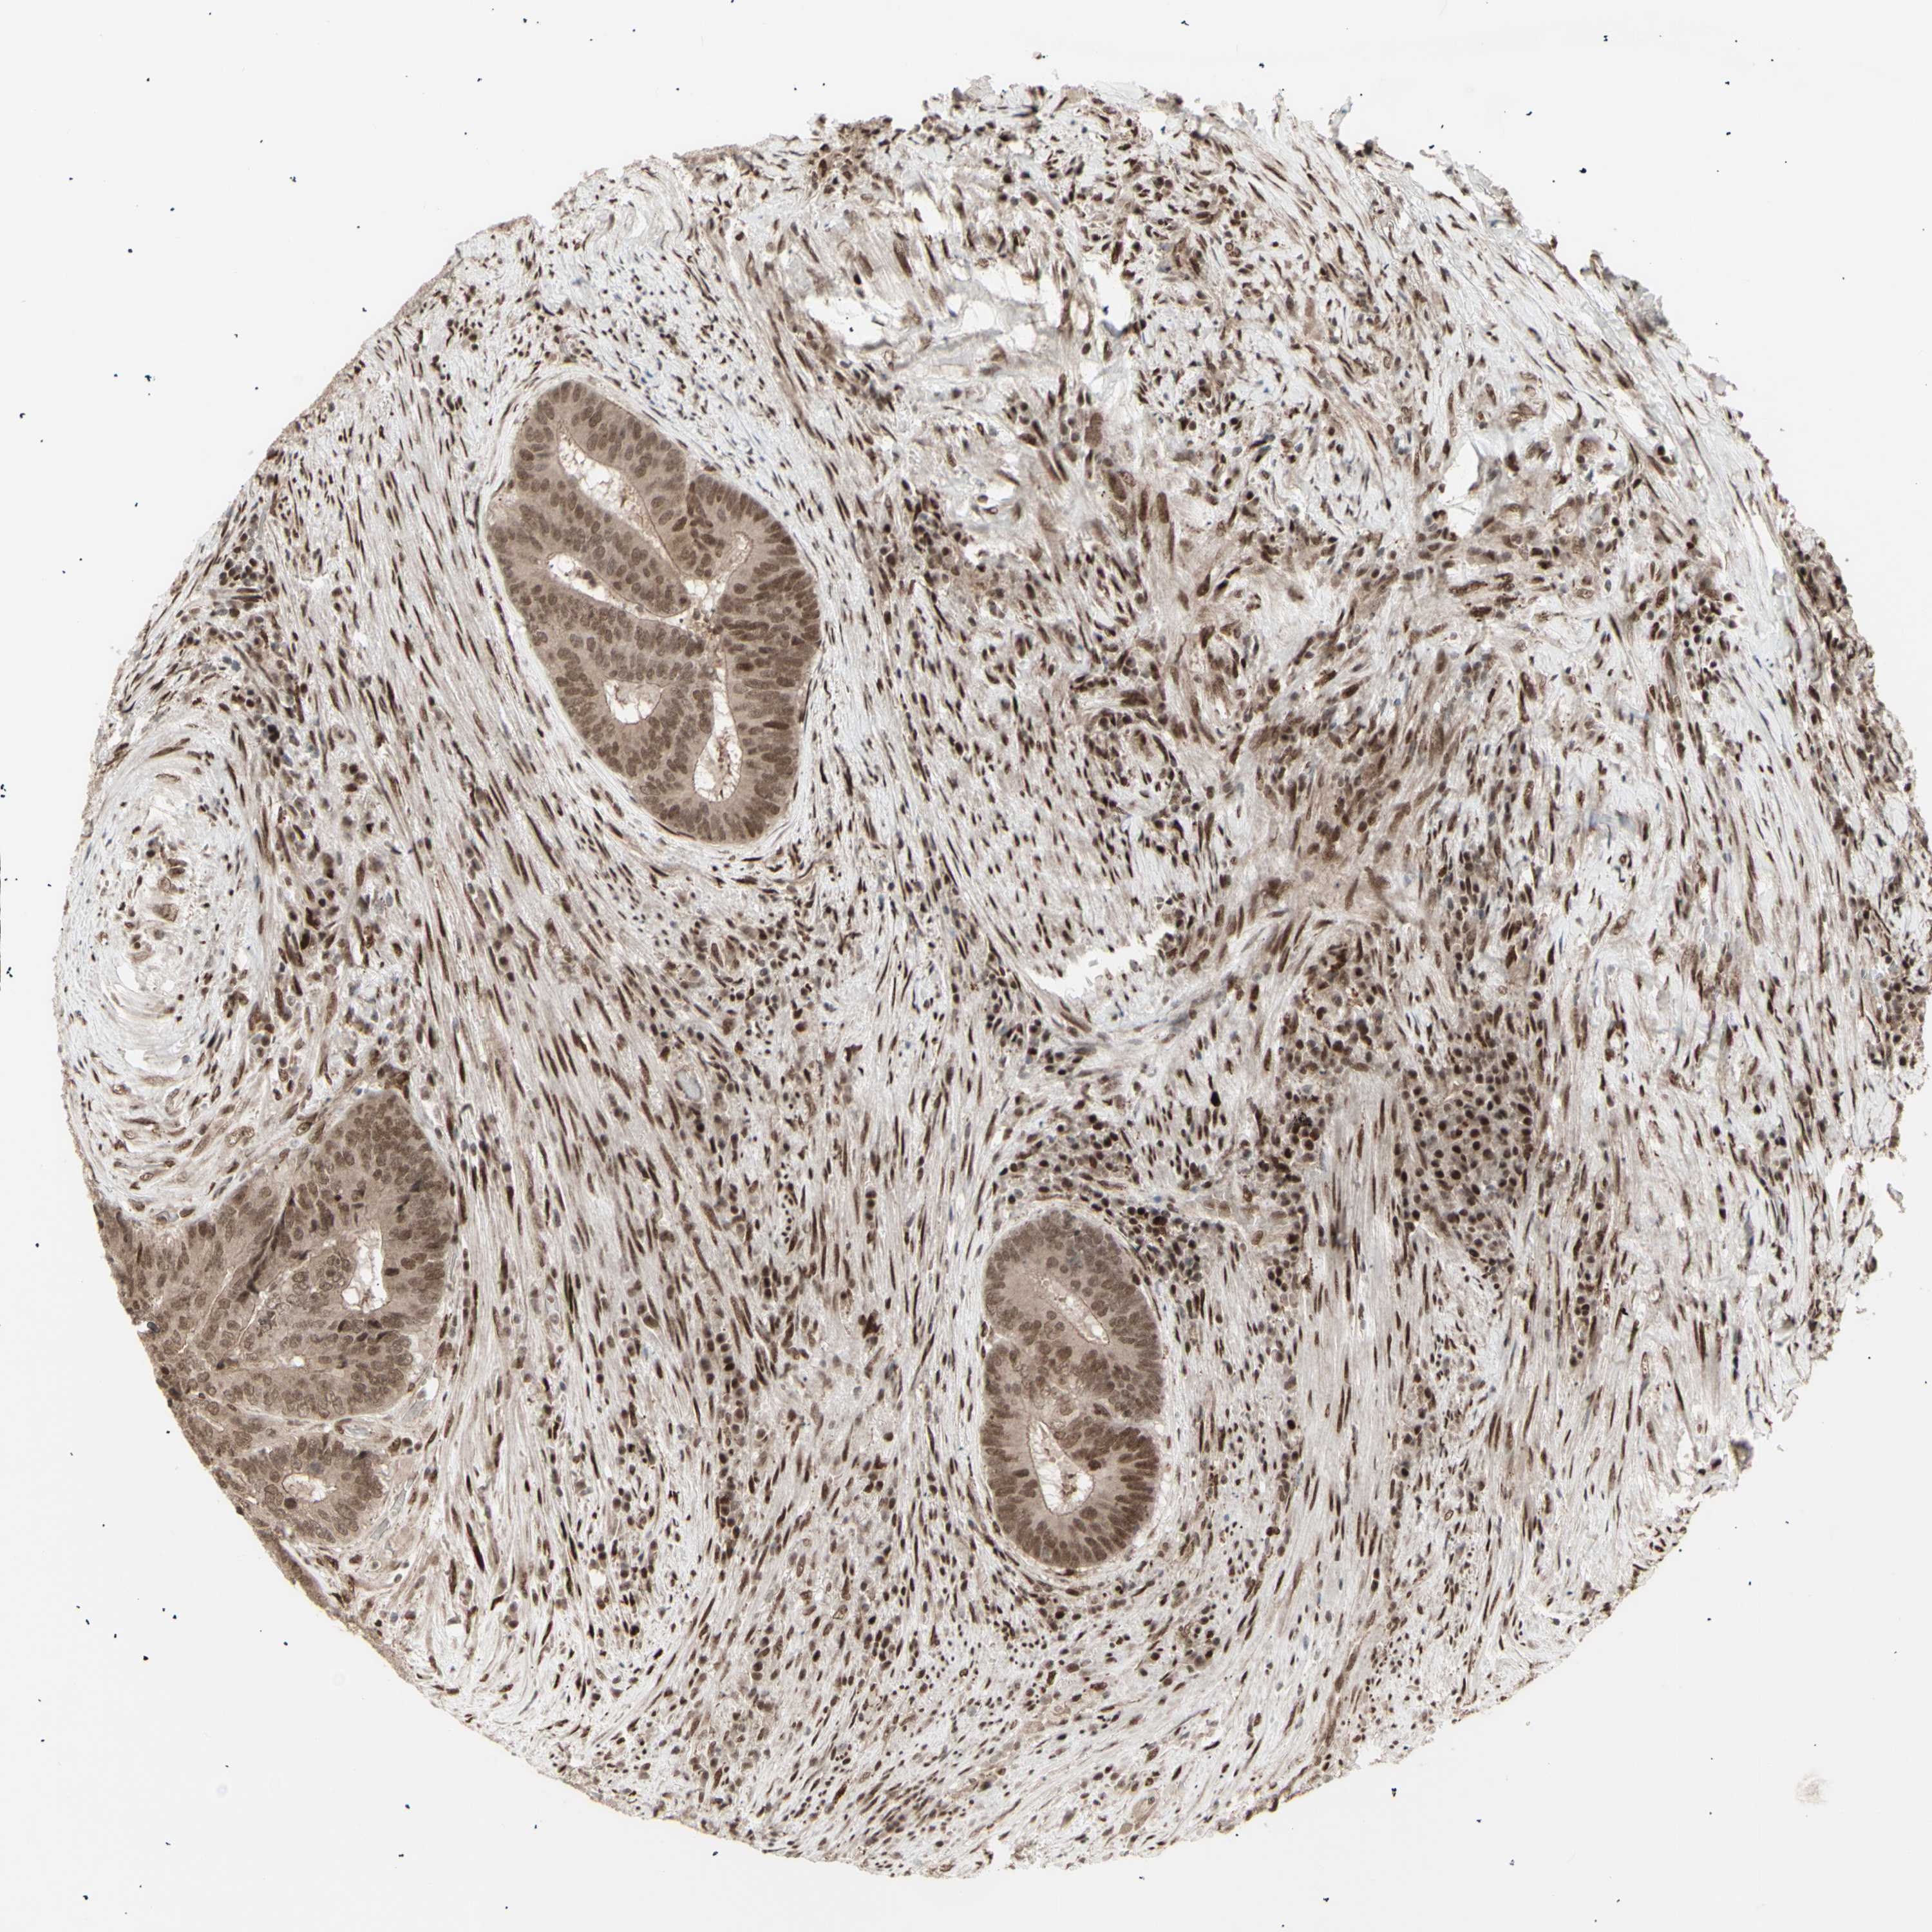

CBX1

CANCER COLORECTAL CANCER Show tissue menu

Colorectal cancer

Colon adenocarcinoma